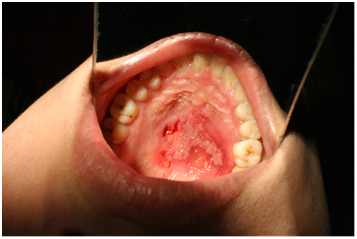

CT Scan of the maxilla revealed erosion of the right half of the hard palate with intranasal extension into the floor of the right nostril with erosion of the adjustant part of the medial wall of the right maxillary antrum upto the base of pterygoid plates and medially the inferior part of the bony part of the nasal septum on that side (Figure 2 & 3). The soft palate was pushed in to the oropharynx. Punch biopsy was taken which suggested Myoepithelioma of minor salivary gland. All preoperative blood and urine investigation was done which were within normal limits. The patient was intubated nasally with endotracheal tube and wide local excision of the mass was done. The tumor was dissected from the nasal mucosa. The excised mass was about 4.5x 3 x2.5cms (Figure 4) and send for histopathological examination. An obturator was given postoperatively.

Figure 6 Postoperative view of patient at 2 months showing complete granulation of palate.